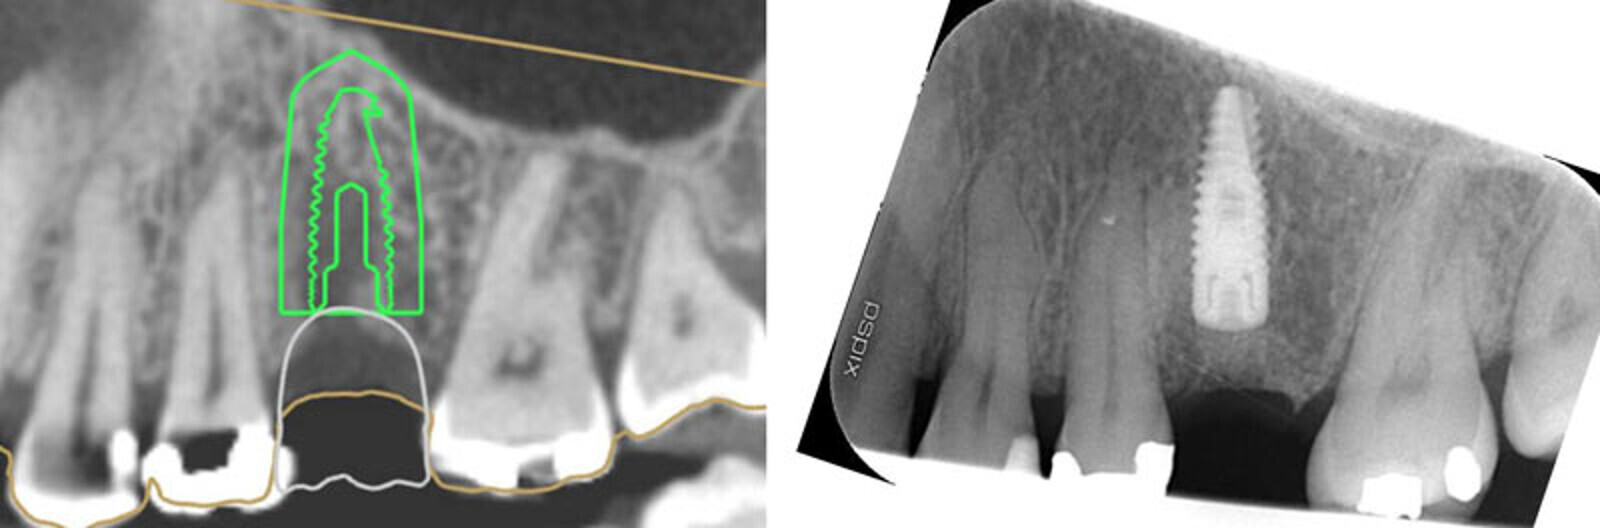

EthOss grafting in fully guided implant placement case with Paltop Guided Implant System. Female 51-year-old patient, non-smoker, non-contributory medical history. Extraction of fractured and infected 26 carried out 10 months ago. Digital planning showed possible buccal defect, so flap raised and grafting was necessary.

EthOss grafting in fully guided implant placement case with Paltop Guided Implant System. Female 51-year-old patient, non-smoker, non-contributory medical history. Extraction of fractured and infected 26 carried out 10 months ago. Digital planning showed possible buccal defect, so flap raised and grafting was necessary. As expected the buccal bone defect shown on the CBCT was not an actual dehiscence defect, just thin immature bone. In any case the buccal concavity was grafted as usual with EthOss. Very precise, quick and minimally invasive procedure.

Buccal defect, need to raise a flap.